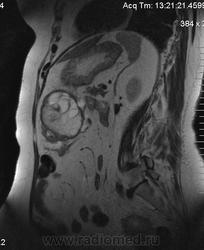

очень характерная картина для метастаза рака яичника, к сожалению.

Не могу достоверно определить локализацию метастаза брюшной полости, вероятно в лимф. узел с инвазией оободочной кишки. Рецидив С-r левого яичника думаю, что с инфильтацией левой стенки прямой кишки и культи влагалища, вторичная лимфаденопатия л/у малого таза. каликопиелоуретероэктазия (инвазия нижних отделов левого мочеточника?) Холедох широковат, но желтухи по внешнему виду нет.

Прорастание левого мочеточника рецидивной опухолью есть 100%, метастаз в большой сальник характерен для рака яичников, как и сигнальные характеристики его. Культя в данном случае шейки матки.